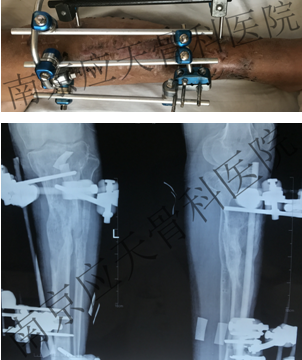

术前:

术后: